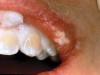

The whitening agents are available in various concentrations ranging from 10% carbamide peroxide (equal to 3.4% hydrogen peroxide) to 38% hydrogen peroxide. If the higher concentration agents contact the soft tissues, they can produce a chemical “burn” that turns the tissues temporarily white (Figure 1 and Figure 2). Although tissues quickly return to their normal color once they rehydrate, they may be mildly uncomfortable for a few hours. The patient may be distressed by the temporary appearance of the whitened soft tissues. A rubber dam or other protective barrier is mandatory to effectively seal off the tissues (Figure 3). In-office systems usually supply a light-cured resin in a syringe to apply around the cervical areas to confine the agent to the teeth (Figure 4 and Figure 5). In addition, flexible spreaders should be placed in the mouth to prevent the cheeks or lips from contacting the whitening agent.

Figure 2  Soft-tissue chemical burns near the left commissure of the mouth and along the free gingival margin due to exposure to the whitening agent.

Figure 2